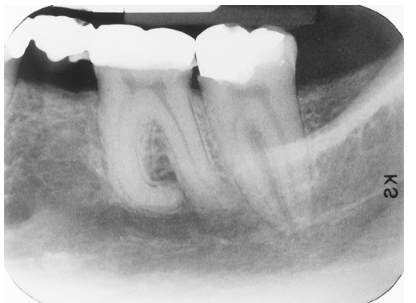

Select the most appropriate term for the anomaly associated with the 1st molar.

diastema

concrescence

dilaceration